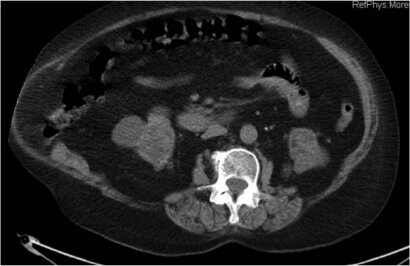

Hernia incisional lumbar asociada a tumor intramuscular (oblicuo externo)

Se presenta el caso de una eventración de gran tamaño (>10 cm) asociada a un tumor intramuscular del oblicuo externo no filiado después de varias punciones. Se describe la historia clínica y se muestra el estudio de imagen completo.

a) El tumor: en la TAC parece tratarse de un tumor sólido , probablemente un desmoides, pero hay que descartar lipoma, liposarcoma, swanoma, etc. no parece metástasico ya que se entiende que el estudio de extensión fué negativo en la paciente y la nefrectomía por el tiempo en proceso benigno.

Caso interesante de combinación de patología de pared (hernia lumbar+tumor sólido). Al igual que comentan los colegas previos seria interesante conocer la causa de la nefrectomía previa, ya que si fue un tumor maligno habría que descartar previamente extensión a distancia. Una vez descartado y si solo se trata de un tumor de la pared abdominal, en nuestro protocolo de actuación y con las pruebas negativas que se presentan, quizás hubiésemos solicitado una RMN, esta prueba es muy útil en tumores de partes blandas y puede hacer una orientación diagnostica preoperatoria.